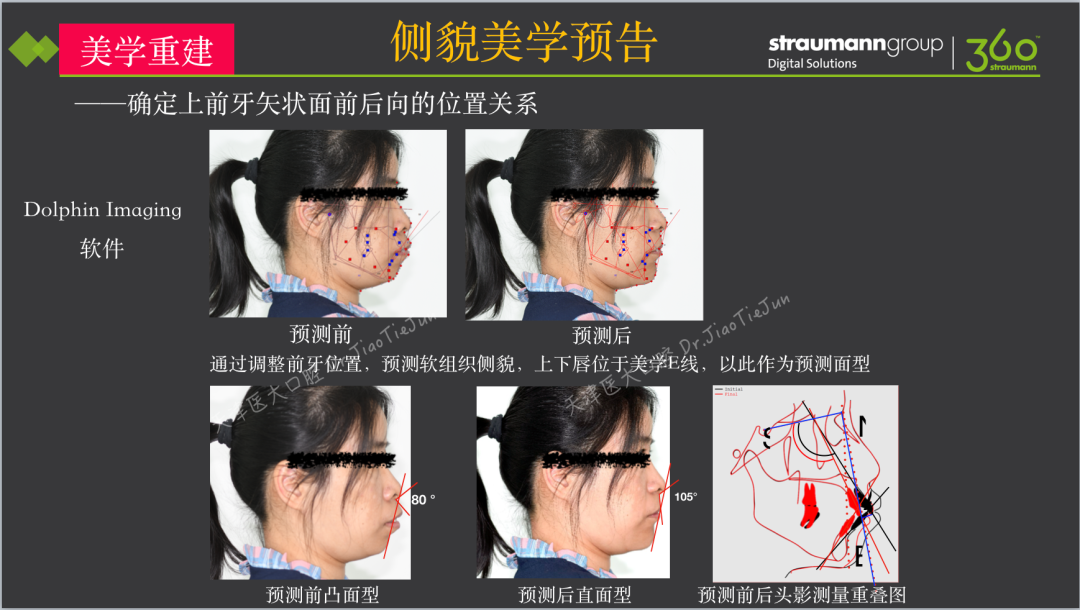

本病例为年轻女性患者,由于口内多牙缺失、多牙松动伴上颌前突多年,寻求治疗方案。通过检查诊断为牙列缺损、重度牙周炎、上颌前突、骨性二类错合畸形,具有上颌骨及上下牙前突、正侧貌美学不佳的临床特点,传统治疗方案,无法预测患者的预期治疗效果,因此采用多种数字化的手段,包括DSD微笑设计、Dolphin Imaging软件进行正侧貌美学预告、士卓曼360数字化序列导板的全方位解决方案,确保此复杂病例最终获得了一个满意的效果。

侧貌美学评估:

· 上唇丰满度:过度,鼻唇角80 °(鼻唇角正常范围:90 °-105 °),上下唇超出美学E线,凸面型;

1) 美学重建的难点:正侧貌美学预告及上前牙三维位置的确定;

· 然后,进行侧面美学预告。

· 侧貌美学预告后,确定了上前牙矢状面前后向的位置关系,中切牙在矢状面上的位置变化:将唇倾的上前牙直立,上中切牙角度减小12度,切端内收8mm。

· 上唇丰满度:适中,鼻唇角105°,上下唇位于美学E线,直面型。

· 预告面型及修复后与修复前对比,患者的正侧貌美学得到了极大的改善,凸面型变为直面型。